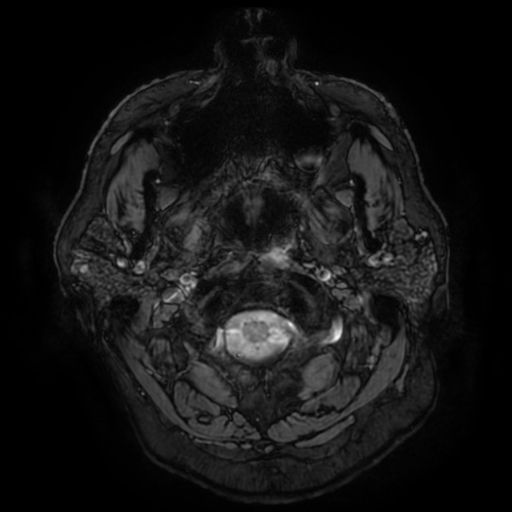

SEQUELAS DE TCE MODERADO-GRAVE — LAD GRAU II COM GLIOSE PONTINA E ATROFIA CEREBRAL PÓS-TRAUMÁTICA

• Compatível com: Microbleeds identificados nas imagens SWI + LAD Grau II + Gliose pontina

• Padrão consistente com LAD Grau II: lesões juxtacorticais + tronco cerebral